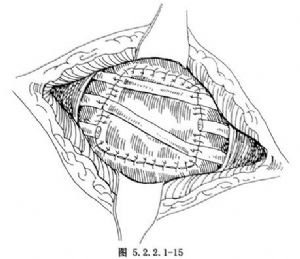

也可將自體肋骨縱行劈成兩半,架橋固定在缺損肋骨的兩端。加強胸壁的穩定性,減輕反常呼吸(圖5.2.2.1-15)。